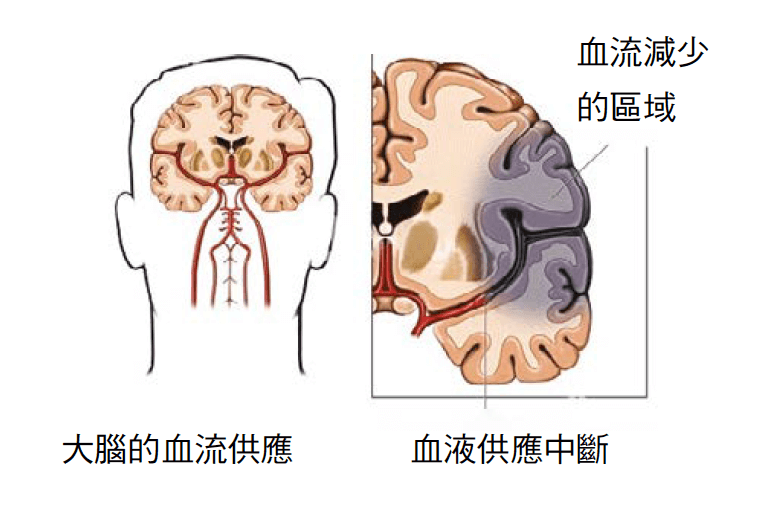

Previous articles, I shared the prevention of stroke, the first aid of ischemic and hemorrhagic stroke, and this time I would like to talk to you about stroke rehabilitation treatment. In addition, it is also important to find out the cause of the stroke in details and prescribe the right medicine to avoid another stroke in the future.

In general, the first three days after a stroke are a turning point for a patient to improve, and the first three weeks are a critical period to determine whether the patient will continue to survive. As for the first three to six months after stroke, it is the golden period of patient recovery, which determines whether they would be permanently disabled. Complications of stroke, particularly cerebral edema and increased intracranial pressure, usually subside within three to four weeks after stroke, and if patients survive this time, the risk of losing their lives decreased. But although they can survive, the stroke patients can become normal resume daily life, or a stroke survivor with mild disability or serious disability, or in vegetative mode who is bed resting for rest of their lives, the outcome depends on the degree of permanent damage caused by the stroke and its complications to the patient’s brain! Whether it is an ischemic stroke or a hemorrhagic stroke, the neurosurgeon will treat complications derived from stroke through first aid, medication or surgery, minimize the permanent damage caused to the brain, let the injured brain have basic functions to maintain life, given the opportunity to slowly recover, so when the nerve function has the opportunity to recover in the first three to six months, the patients need to cooperate with traditional acupuncture, physical therapy. Rehabilitation courses such as speech therapy and occupational therapy. In other words, if the patient’s brain damage is severe, and it has reached the stage of severe disability, then all of the above traditional treatments are in vain.

Ms. Li, a 69-year-old housewife with history of diabetes, high cholesterol and high blood pressure, has been following up and taking medication in public hospitals. When she woke up one morning two years ago, her children found that she had difficulty speaking and that her right hand and foot were weak, so they urgently called an ambulance to take her to the emergency room. After a CT scan, the doctor’s diagnosis was an ischemic stroke in the left side of the brain. During the two-week of hospitalization, Ms. Li’s daugther found that her mother’s condition not only did not improve, but also deteriorated, gradually becoming unable to speak, and her right hand and foot were gradually unable to move, so they admit their mother to a private hospital for continued care. Detailed brain MRI showed that the blood vessels in Li’s left brain were seriously damage, resulting in a large necrosis of her left brain due to ischemic stroke, so that her speech ability and the strength of her right hand and foot became worse